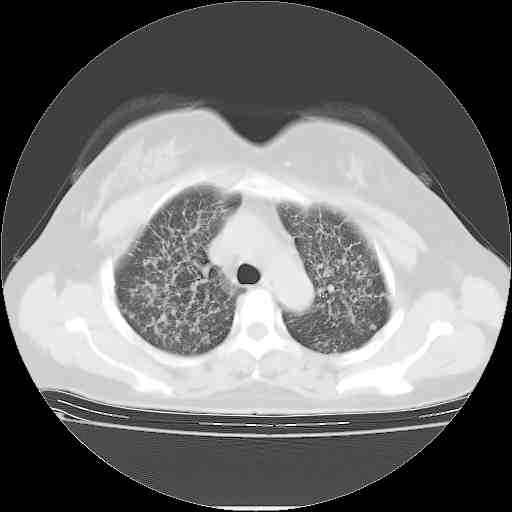

下面是今天刚刚做的,在上海治疗,吃了家属也说不清的一种药,一个月1万左右,

考虑  腺癌肺内转移,治疗较前病灶缩小、减少

肺癌并肺内转移,这种疾病治疗后在影像上看略有好转,不是很显著,但是肿瘤治疗效果影像只是一方面。

支持右肺下叶周围型肺癌并肺内淋巴管炎,  原发灶小了,但转移较前片明显了.。

标准的细支气管肺泡癌呀!治疗后病情有所控制,也没治愈的迹象!

标准的癌性淋巴管炎!!距大去之日不远已.

应该是比较典型的细支气管炎,4个月的时间不说明问题;有时候疾病是有个相对稳定期的,如果喝10元一斤的茶叶估计也会这样。